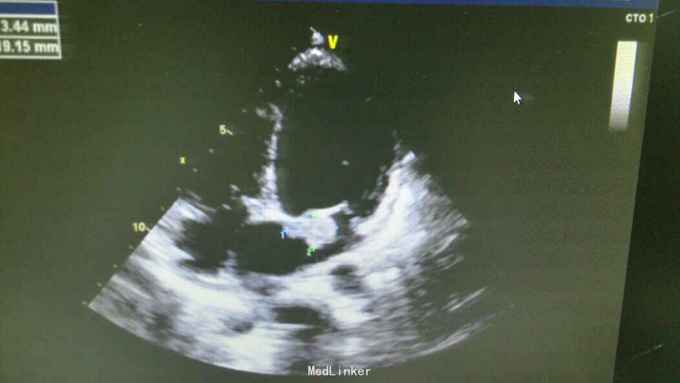

查体:T37.0℃,P110次/分,R26次/分,BP96/68mmHg。发育正常,营养一般,神志清楚,对答切题,轮椅送入院,查体合作。全身皮肤粘膜无黄染、皮疹,出血点及淤斑,未见Janeway结节,未见Osler结节及甲床下出血,无发绀,未见杵状指、趾,周围血管征阴性。浅表淋巴结未及肿大。巩膜无黄染,结膜无出血。口腔黏膜光滑,咽不红,扁桃体部大,颈静脉无明显搏动,未见怒张,气管居中,胸背部听诊双下肺闻及细小湿啰音。心前区无隆起或抬举性搏动,心尖搏动以左侧第六肋间锁骨中线外1.5cm处明显,未扪及震颤,心界向两侧稍扩大,心率110次/分,律齐,心音有力,P2稍亢进,无固定分裂,心尖区闻及3-4/6级收缩期吹风样杂音,向心底部传导,未闻及舒张期杂音,未闻及心包摩擦音。腹平软,无压痛及反跳痛,肝脾肋下未及,肠鸣音正常。脊柱、四肢关节无异常,活动好,双下肢无浮肿。 2015年10月30日汕头市中心医院心彩超:二尖瓣及瓣下腱索及左室心内膜多发赘生物形成,二尖瓣前瓣穿孔,重度二尖瓣关闭不全,左心系统扩大,心肌舒张功能下降,收缩功能正常,感染性细菌性心内膜炎,微量心包积液。 2015-11-1血常规:中性粒细胞比例 0.949,血红蛋白浓度 117.000(g/L),中性粒细胞计数 18.360(10E9/L),白细胞计数 19.350(10E9/L),血小板计数 343.000(10E9/L),红细胞计数 4.350(10E12/L)。 B超:双侧颈动脉血流通畅,双侧椎动脉未见狭窄。双侧甲状腺不大、未见占位,血供尚丰富。双侧颈部淋巴结声像,双侧乳腺未见明显占位,超声BI-RADS分类1类,双侧腋窝淋巴结声像。双肾未见结石与积水,双肾动脉主干血流连续,膀胱未见明显结石,双侧肾上腺区未见明显占位。肝脾胰不大,未见占位,胆囊未见明显结石,子宫及双侧附件区未见明显占位,宫后积液(少量)。 胸部CT:1、两下肺叶后基底段局部节段性肺炎。右肺中叶少许纤维化病灶。2、双侧胸腔少量积液。 胸片:考虑双肺炎症。 心电图:心率84次/分,窦性心律,肢体导联低电压,前间壁R波上升不良。 心彩超:1、考虑感染性心内膜炎:二尖瓣赘生物形成,伴中重度二尖瓣反流。中度三尖瓣反流。3、左房内径增大,肺动脉增宽。 头颅MR:左侧额叶、左侧放射冠侧脑室前角旁脑白质异常信号,考虑感染性病变及缺血灶可能性大。 2015-11-2查血常规:中性粒细胞比例 0.840,血红蛋白浓度 103.000(g/L),中性粒细胞计数 14.730(10E9/L),白细胞计数 17.540(10E9/L),红细胞计数 3.890(10E12/L),血小板计数 353.000(10E9/L)。 10月31日左上肢、右上肢、下肢血培养均提示:草绿色链球菌,对万古霉素敏感。 2015-11-6肾功能:肌酐 130.000(umol/L),尿素氮 5.250(mmol/L),二氧化碳结合力 30.500(mmol/L),电解质:钠 138.000(mmol/L),氯 96.000(mmol/L),钾 3.500(mmol/L),钙 2.310(mmol/L),肝功能:白、球蛋白比例 1.300,未结合胆红素 10.500(umol/L),总胆红素 17.900(umol/L),丙氨酸氨基转移酶 31.000(U/L),总蛋白 75.000(g/L),球蛋白 32.000(g/L),白蛋白 43.000(g/L),结合胆红素 7.400(umol/L),门冬氨酸氨基转移酶 31.000(U/L),脑钠肽:191.400(pg/ml)。 24小时心电图:窦性心律,房性早搏,部分成对,短阵房速,多源室早,部分成对,部分呈三联律,短阵室速。

根据患者病史、查体、辅助检查可明确术前诊断:1、亚急性感染性心内膜炎:二尖瓣赘生物形成,二尖瓣关闭不全(中-重度),三尖瓣关闭不全(中度),心功能Ⅱ-Ⅲ级。2、肾功能不全。3、贫血。予选择敏感抗生素抗感染治疗,先用万古霉素1g q12h+阿米卡星0.3 q12h,抗感染治疗,后查肌酐升高,肌酐 145.000(umol/L),肾功能受损,考虑与万古霉素有关,请临床药师会诊建议调整抗生素,11-8改头孢曲松1g q12h抗感染。另积极强心、利尿、控制心率、营养心肌、提高免疫力、输血等治疗,患者仍间有高热、畏寒,存在肾功能损害、贫血,手术时机不能拖延。2015-11-12全麻体外循环下行左心赘生物清除、二尖瓣置换、三尖瓣成形、卵圆孔未闭修补术。 手术记录: 平卧位,麻醉诱导插管,左桡动脉穿刺置管测血压,右颈内静脉穿刺置管测中心静脉压及输液,留置导尿管,安尔碘消毒皮肤,常规铺巾,贴皮肤保护膜。正中切口,纵锯胸骨进胸,正中切开心包,术中探查:少-中量淡黄色心包积液,右心房、右心室明显增大,主动脉:肺动脉=22:28(mm),肺动脉扪诊张力较高,主动脉根部无震颤。常规主动脉、上、下腔静脉套带,缝合荷包,上腔静脉荷包用4-0prolene线缝在上腔静脉根部。肝素化(3mg/kg),依次插主动脉管(20号)、上腔管(26号金属直角管)、下腔管(32号),转机并行循环,右上肺静脉插左心引流管,主动脉根部插灌注针。阻断上、下腔静脉,阻断主动脉,顺灌4:1含血停跳液300ml,心表冰泥降温保护心肌,心脏停跳,纵形切开右房见卵圆孔未闭,切开房间隔,探查见二尖瓣败坏严重,前瓣靠瓣沿有一较大赘生物,瓣下腱索上也有芝麻粒大小赘生物,后瓣靠前交界瓣叶上右大小不等赘生物,腱索挛缩,将瓣叶及赘生物粘在左室后壁,瓣口关闭不全,左房后壁靠瓣环前交界附近有散在的米粒或芝麻大小赘生物,无附壁血栓。切除病变瓣膜及腱索,仔细清除左心室、瓣环及左房后壁赘生物,高效碘消毒左心腔,大量冰生理盐水反复冲洗左心室,测量瓣环可容27号,全周带垫片褥式缝合14针,再次冲洗左心室,用carbomedics 27号瓣,上瓣打结,检查瓣膜固定满意,瓣叶开闭正常,将左心引流管通过瓣口置入左心室内,用4-0prolene线封上下角后连续往返缝合房间隔切口,修补未闭卵圆孔。探查三尖瓣环扩大达3横指多,用3-0proline线带垫片缝缩三尖瓣后瓣环(半个devage成形),做三尖瓣成形至能通过约2个横指,主动脉灌注针及左心管排气,开放主动脉阻断钳,心脏自动复跳,为结性心率,心率慢,约50-60次/分。用4-0prolene线关闭右心房切口。辅助循环后转为窦性心律。复温及并行循环辅助后血流动力学稳定停机,依次拔出左心管、下、上腔管,主动脉根部注射鱼精蛋白,拔出主动脉管,检查心脏各切口并止血,心脏各切口覆盖艾薇停(1包)、胶原蛋白海绵(2包),3-0滑线连续缝合心包,电烙骨腊止血,留置心包及纵膈引流管,5根钢丝对合胸骨,逐层缝合关胸,术毕。 术后继续孢曲松1.5g q12h+庆大霉素4万U q8h抗感染,另积极强心、利尿、控制心率、营养心肌、抗凝、提高免疫力、补充营养等治疗,患者无发热、寒战,全身状况好转,但出现反复双侧胸腔积液及心包积液,予心包穿刺引流及胸腔闭式引流。目前患者在平稳恢复中,治愈出院。